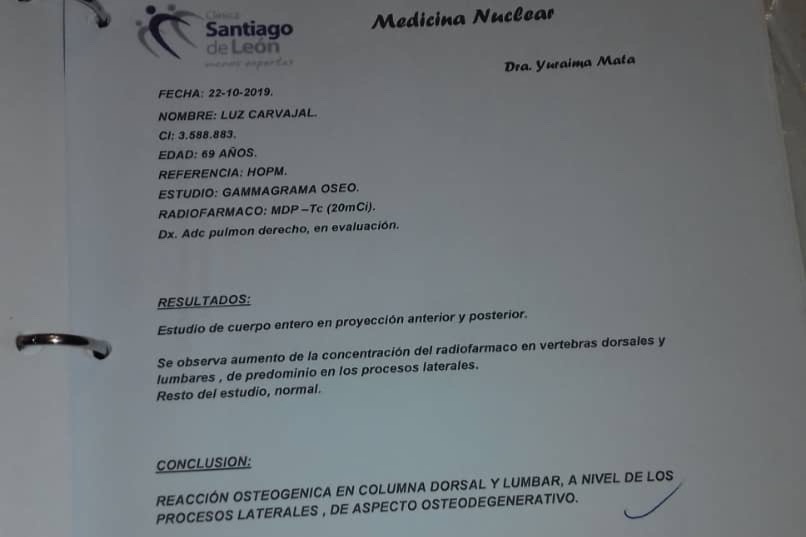

En septiembre de 2019 fue diagnosticada con cáncer de pulmón con una Lesión Ocupante de Espacio (LOE) de 2,5 cm y otra lesión en el Mediastino de 5,4 x 4,7 cm.

A continuación les dejo el diagnóstico, los exámenes, y los presupuestos de los próximos exámenes que hay que hacerle a mi mamá.

In September 2019, she was diagnosed with lung cancer with a Space Occupying Injury (LOE) of 2.5 cm and another lesion in the Mediastinum of 5.4 x 4.7 cm.

Down here I leave the diagnosis, exams, and budgets for the next exams to be done to my mom.

En septiembre de 2019 fue diagnosticada con cáncer de pulmón con una Lesión Ocupante de Espacio (LOE) de 2,5 cm y otra lesión en el Mediastino de 5,4 x 4,7 cm.

A continuación les dejo el diagnóstico, los exámenes, y los presupuestos de los próximos exámenes que hay que hacerle a mi mamá.

In September 2019, she was diagnosed with lung cancer with a Space Occupying Injury (LOE) of 2.5 cm and another lesion in the Mediastinum of 5.4 x 4.7 cm.

Down here I leave the diagnosis, exams, and budgets for the next exams to be done to my mom.